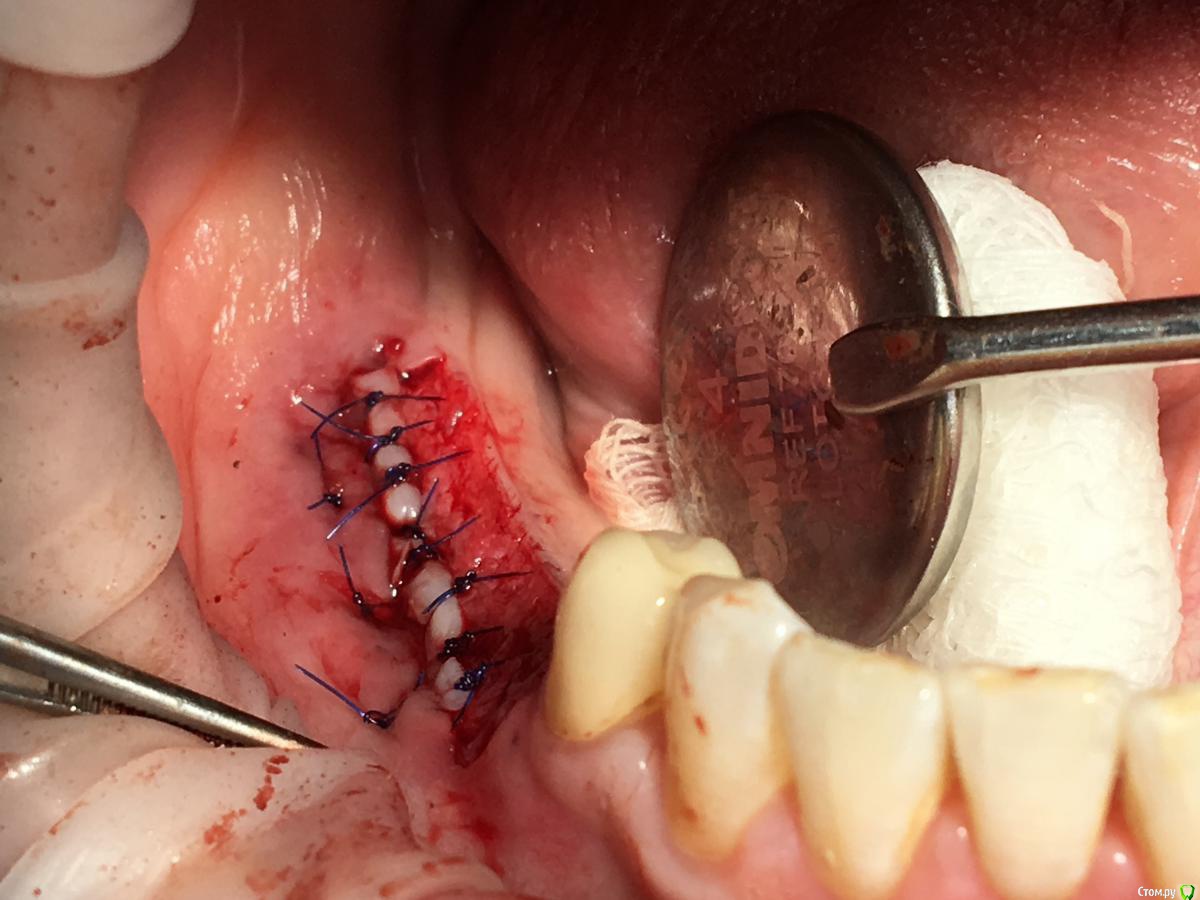

Shakirbura Опубликовано 4 мая, 2018 Автор Поделиться Опубликовано 4 мая, 2018 Закончу кейс, раз уж начал...Оставил импланты на 4 месяца.Провел смещение лоскута, а через месяц раскрыл с ФДМ и ССТ.Вот что получилось. Всем спасибо. 7 Ссылка на комментарий

Bier Опубликовано 4 мая, 2018 Поделиться Опубликовано 4 мая, 2018 ну ничего так косточка то наросла )) Ссылка на комментарий

Shakirbura Опубликовано 4 мая, 2018 Автор Поделиться Опубликовано 4 мая, 2018 ну ничего так косточка то наросла ))Да, душевная) Только целый год на это дело потратили..... Ссылка на комментарий